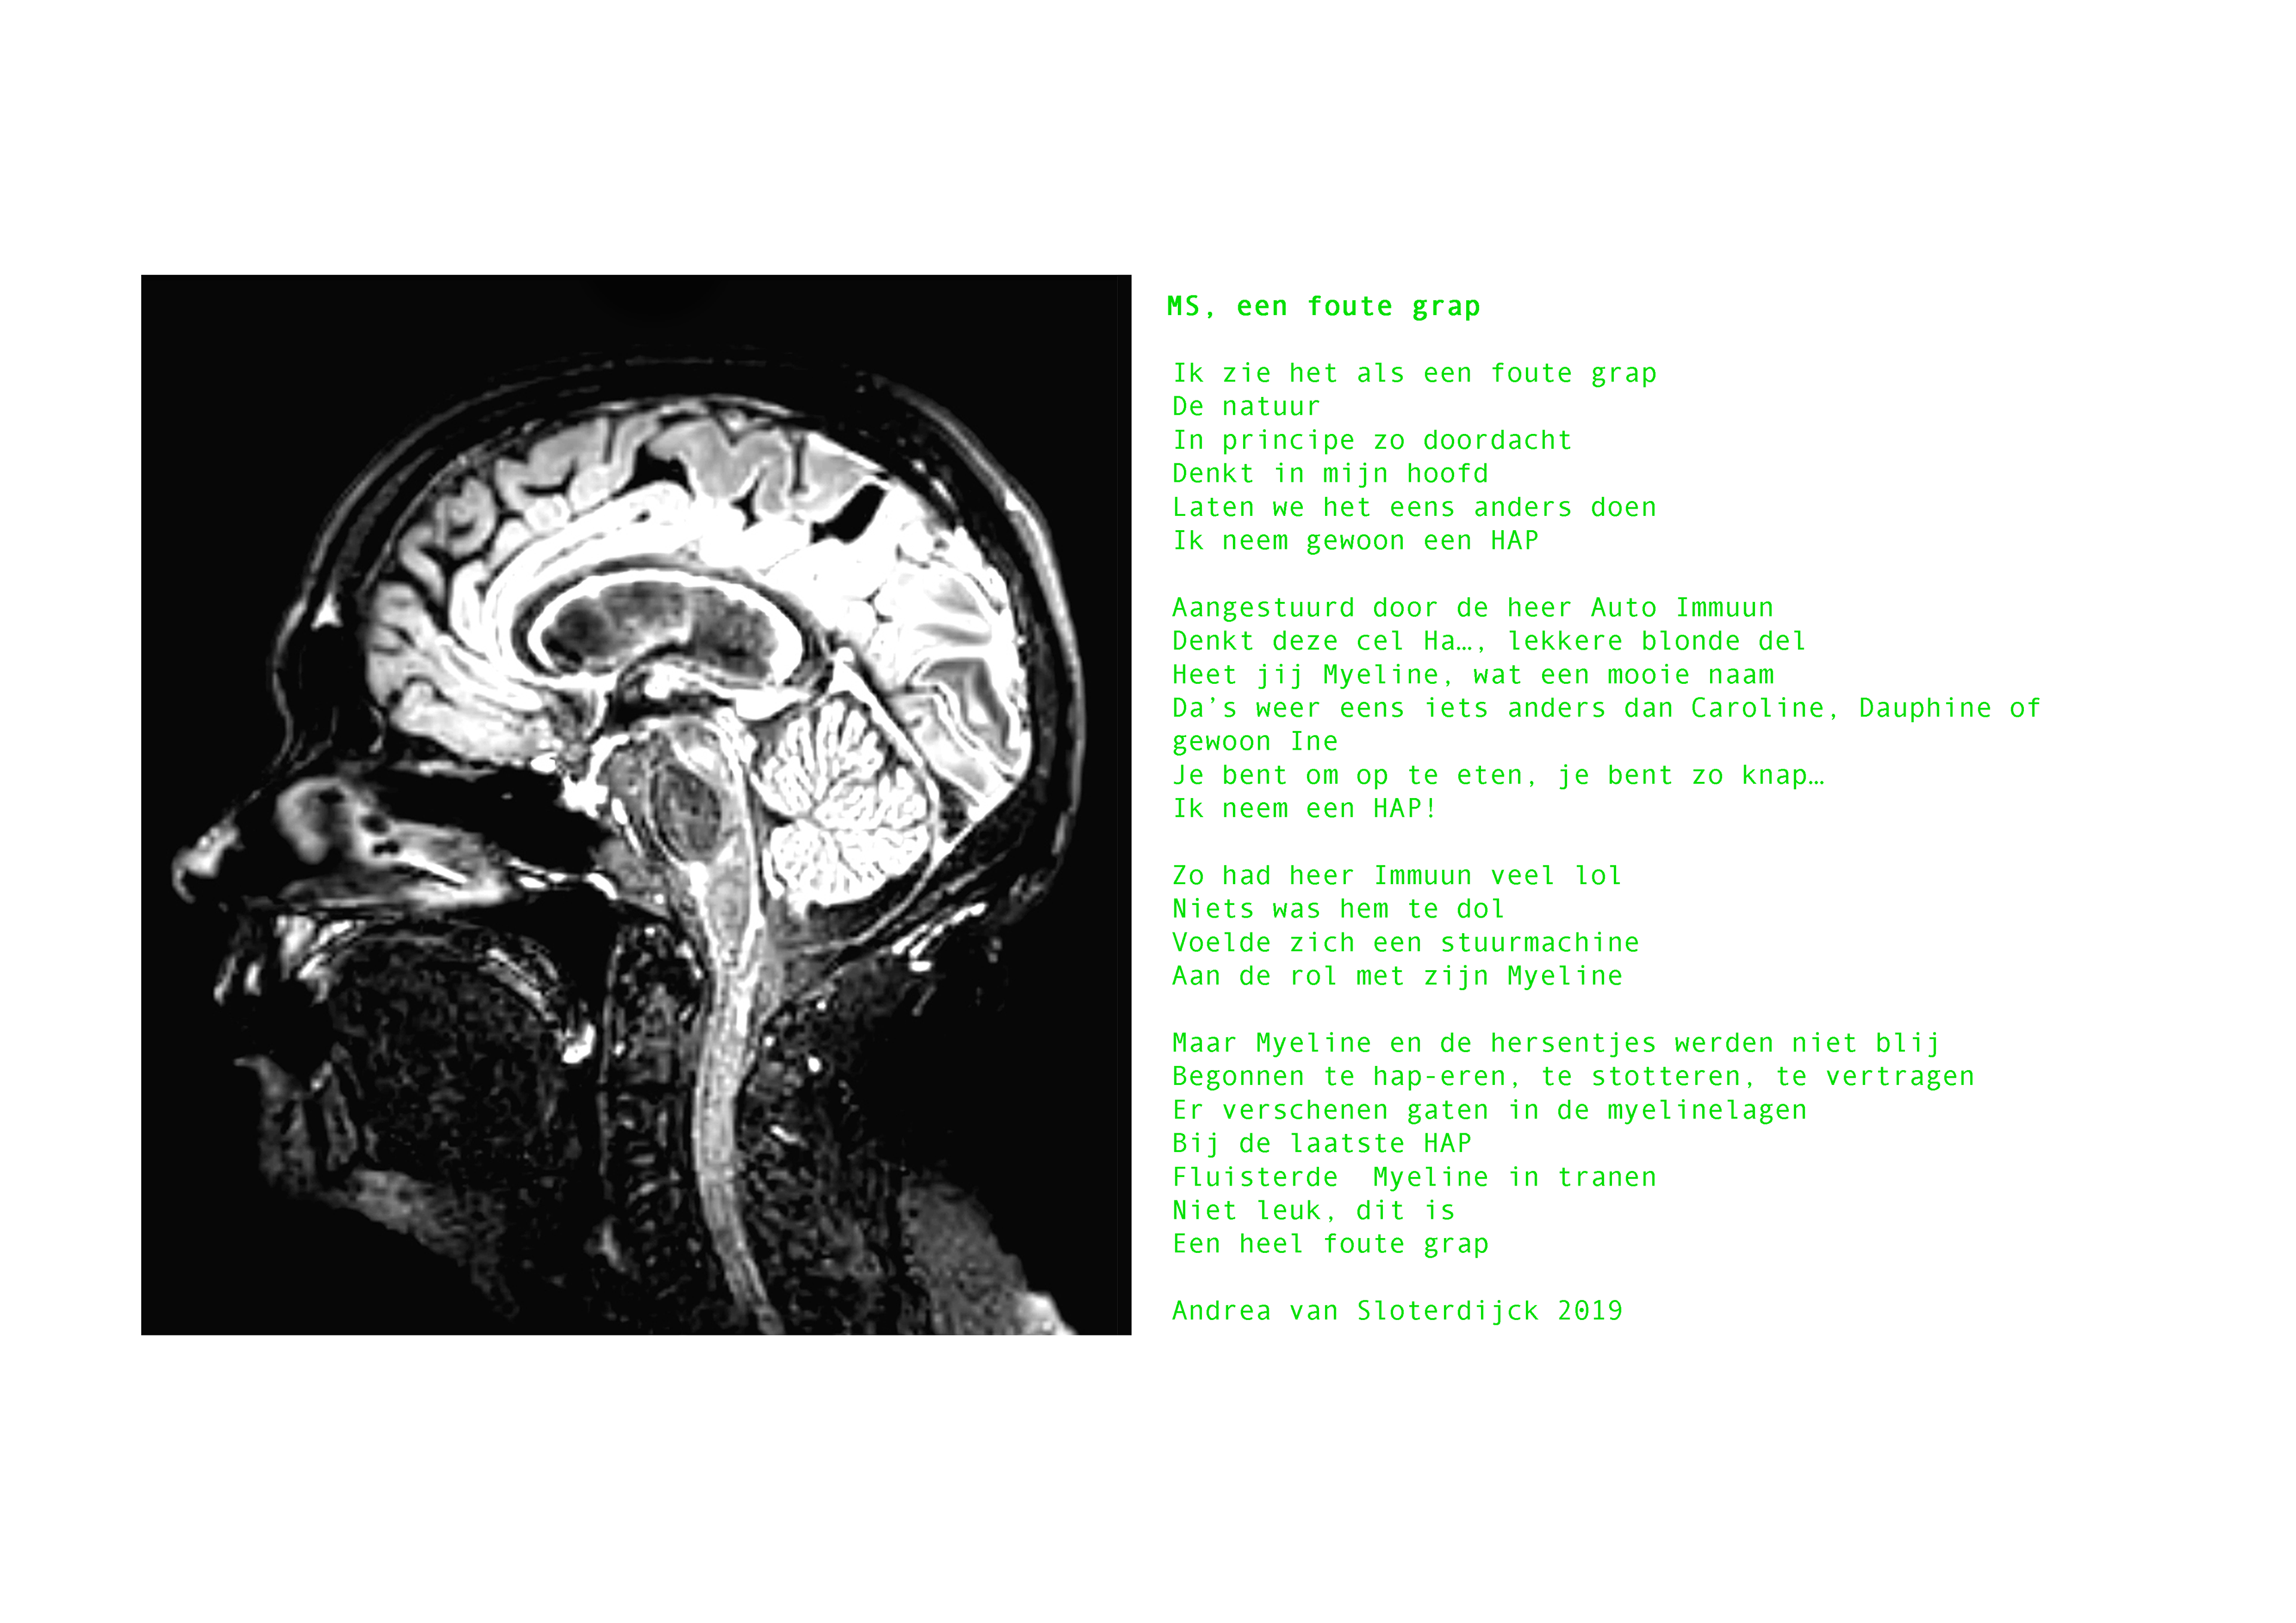

In een gezamenlijk kunstproject met drie andere vrouwen met MS, Marta Lameris, Andrea van Sloterdijck en Lisette Oliemeulen, onderzocht ik de veilige ruimte voor het delen en onderzoeken van persoonlijke ervaringen met de chronische ziekte doormiddel van dialoog en verbeelding. Centraal stonden de vragen;